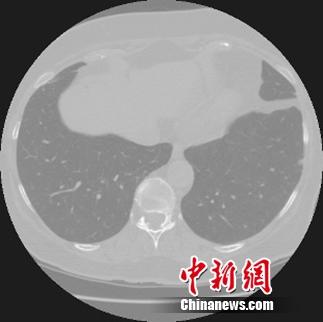

中新网3月29日电 今日,阿里云与英特尔、零氪科技联合宣布启动天池医疗AI大赛。大赛第一季将向早期肺癌诊断发起挑战。

天池是全球规模最大的众智平台,汇聚了6万多名AI算法科学家。医疗大数据平台零氪科技为大赛提供经脱敏处理并由专家标注的高清胸部CT扫描影像数据。选手需要通过原始CT影像图片训练模型算法得到结节特征,最终实现对影像图片结节区域的智能化判断。

结节是影像学上的一个描述性名词,只有在发现结节之后才能进一步确认是良性还是恶性。因此,对于肺癌的筛查来说,准确发现结节是诊断的第一步。

一位经过严格训练,有着多年临床经验的医生,诊断一个病例平均需要查看200张以上的CT扫描图片,诊断时间在20分钟以上。而计算机结节检测系统通过学习大量有经验医师标注的样本,能在短时间内快速提升诊断能力,辅助基层医疗机构的医生减少误诊。